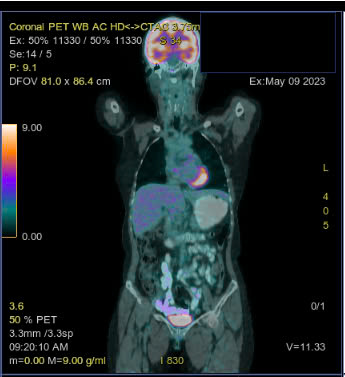

Sau điều trị 4 chu kỳ, bệnh nhân được chụp PET/CT đánh giá đáp ứng điều trị:

Hình 4. Hình ảnh không còn thấy hình ảnh tổn thương hạch và ngoài hạch (so phim trước điều trị).

Kết luận:

– Không thấy hình ảnh tăng chuyển hóa ở tiểu khung

– Hình ảnh tăng chuyển hóa FDG lan tỏa ở tủy xương đốt sống ngực, thắt lưng, xương chậu 2 bên do phản ứng.

– Hình ảnh vài dải mờ và đám kính mờ phân bố rải rác nhu mô 2 phổi, không tăng chuyển hóa FDG.

Theo thang điểm 5-PS, bệnh nhân có đáp ứng là điểm 1 tại các tổn thương. Bệnh đáp ứng hoàn toàn trên PET/CT.